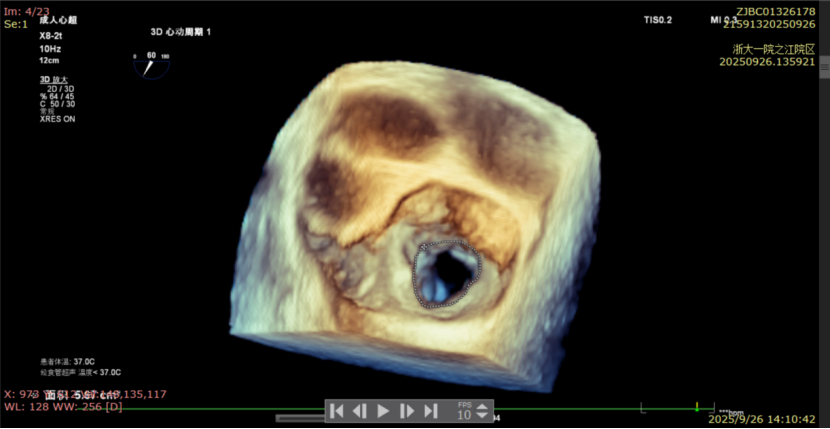

术前经食道超声显示:二尖瓣C1、P1区脱垂,重度关闭不全,彩色多普勒提示大量二尖瓣反流。术前瓣口面积MVA约5cm²,瓣环前后径AP约36.9mm,前叶A1约26mm,后叶P1约15.2mm。